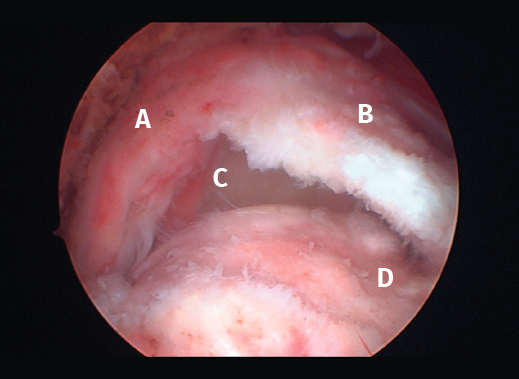

Figura 3. Rotura del manguito rotador en forma de L. A: tendón infraespinoso; B: tendón supraespinoso; C: glena; D: cabeza humeral.

Figura 5. Rotura de tipo C1. A: rotura pequeña de espesor completo del supraespinoso; B: cabeza humeral.

Sin embargo, las clasificaciones basadas en el tamaño de la rotura deben ser bidimensionales, ya que la visión unidimensional puede ser engañosa, al mostrar el tamaño de la rotura solo desde el plano anteroposterior(4). Por esta razón, proponemos el sistema de clasificación del manguito posterosuperior sugerida por Snyder, que aporta información no solo del tamaño, sino del número de tendones afectados y la presencia de tejido cicatricial(7). En las lesiones de tipo C1 la lesión atraviesa todo el espesor del tendón y en el eje transversal es pequeña y punzante (Figura 5). Las de tipo C2 son roturas de espesor completo pero la distancia entre los extremos de la rotura es menor de 2 cm con escasa retracción (Figura 6). En las de tipo C3 la rotura afecta en sentido transversal entre 3 y 4 cm con mayor retracción implicando 2 tendones (Figura 7). Y las de tipo C4 son la rotura masiva del manguito de los rotadores con una afectación de espesor completo de toda la anchura de 2 o más tendones asociando importante retracción (Figura 8).